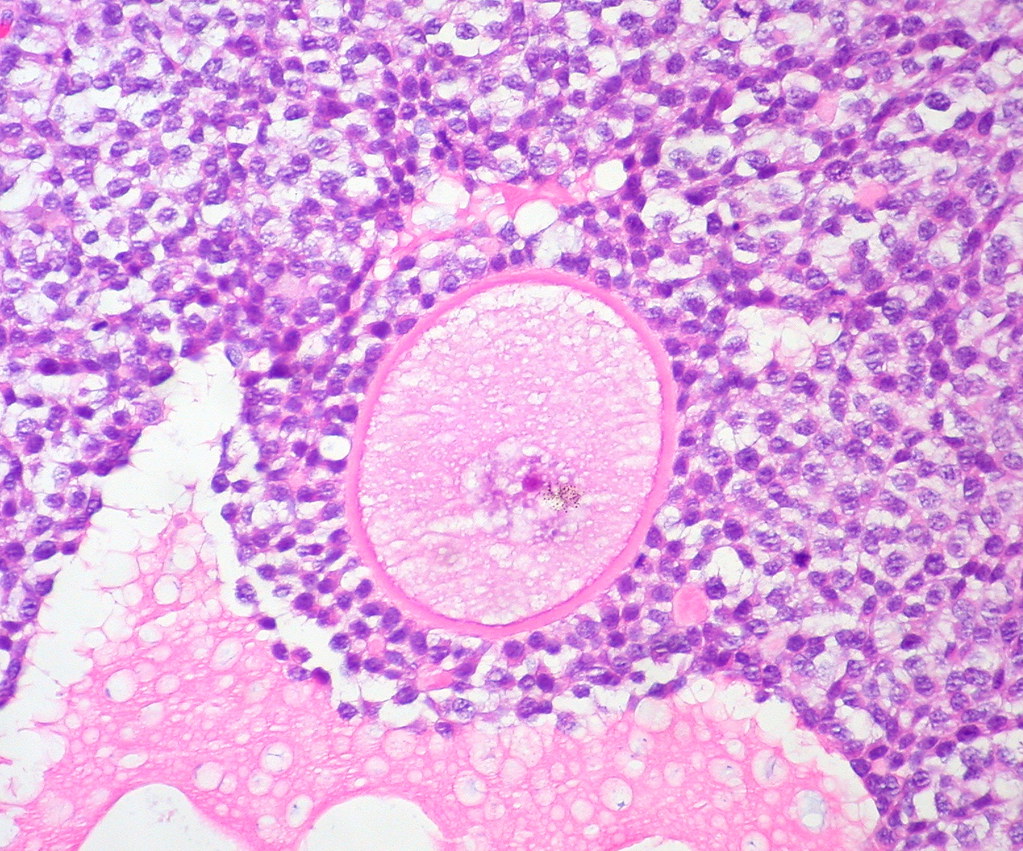

Zaraz po zakończeniu miesiączki w Twoich jajnikach zaczyna się fascynujący proces. Kilka pęcherzyków jajnikowych (zwanych pęcherzykami Graafa) rozpoczyna wyścig o dominację. Zazwyczaj tylko jeden z nich – ten największy i najbardziej dojrzały – dociera do mety.

W tym pęcherzyku znajduje się komórka jajowa, która przez około dwa tygodnie dojrzewa pod wpływem hormonu folikulotropowego (FSH). Pod koniec drugiego tygodnia ciąży pęcherzyk osiąga średnicę około 20-25 mm i jest gotowy do pęknięcia.

Około 14. dnia cyklu (u kobiet z regularnym 28-dniowym cyklem) następuje gwałtowny wzrost hormonu luteinizującego (LH). Ten hormonalny skok powoduje pęknięcie pęcherzyka Graafa i uwolnienie dojrzałej komórki jajowej.

Po owulacji pozostałości pęcherzyka Graafa przekształcają się w ciałko żółte, które produkuje progesteron. Ten hormon dalej pogrubia błonę śluzową i sprawia, że jest ona bogata w substancje odżywcze – gotowa na przyjęcie zapłodnionej komórki jajowej.